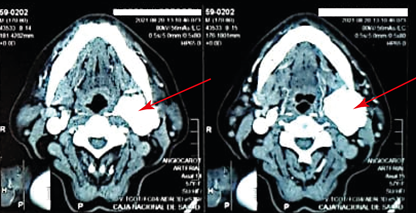

La Tomografia Axial Computalizada (TAC) de región carotidea y submaxilar, en cortes axiales y coronales de 5mm de espesor e intervalo, se evidencia carótida común hasta base de cráneo. A nivel de la bifurcación de la carótida común izquierda en carótida interna y externa se observa una imagen nodular de contornos lobulados, aspecto homogéneo en fase simple, tras la administración de contraste, presenta marcado realce arterial y venoso pero de aspecto heterogeno por la presencia de áreas centrales hipocaptantes que no realzan que podrían corresponder a aéreas de necrosis, esta lesión mide 54x37x32 mm y rodea en 180° a las arterias carótidas interna y externa, además ejerce efecto de masa y comprime parcialmente la vena yugular ipsilateral.

La Tomografía Axial Computarizada de la paciente informa: Se observa imagen tipo nodular en carótida interna y externa izquierda con marcado realce al medio de contraste y áreas de aparente necrosis que corresponde a Glomus carotideo izquierdo tipo II. Según la literatura la introdujo Shamblin (Clasificación Glomus basada en el tamaño grupo I, II, III)15.

Un estudio propone la clasificación de acuerdo al tamaño del tumor para una posible conducta TAC de la Clasificación de Los Andes (ciudad de La Paz)17. También hay el diagnóstico usando la TAC de cuello con contraste endovenoso y Angio-TAC5. En el presente caso también se observa el tumor con este tipo de estudio de imagen. Y la arteriografía sigue siendo el método elegido diagnóstico como signo patognomónico (signo de la lira)2,6,10,12.